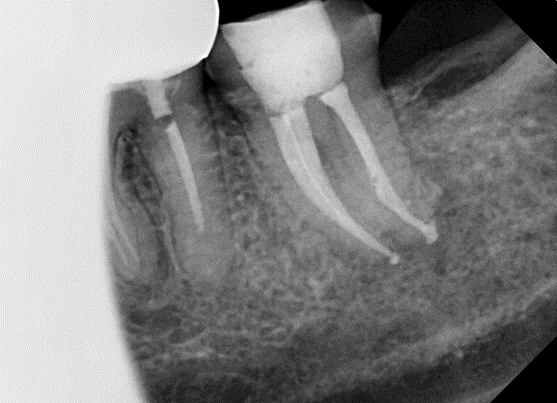

![[신경치료] 아래 어금니를 신경치료 할 때 치료할 때 알아야 할 것 (C형근관,고난이도치료) 관련 이미지 10](https://pub-9f2bb3498faf4d1d8714b41df24753e3.r2.dev/content/clinics/archive/nqmm0udu86/naver_blog/honeybeevuvu/assets/by_hash/d394d56c30560fcc5ca8c52eb5a94846c71e2e04c9dac8d1a9beef9183d30831.png)

본원의 C형 근관 치료 예시 -20대 남성

어느 것 하나 같은 모양이 없습니다.

물론 C형근관의 표준적인 카테고리는 존재합니다.

그러나 늘 방심하지 않고 꼼꼼하게 치료하고자 노력합니다.